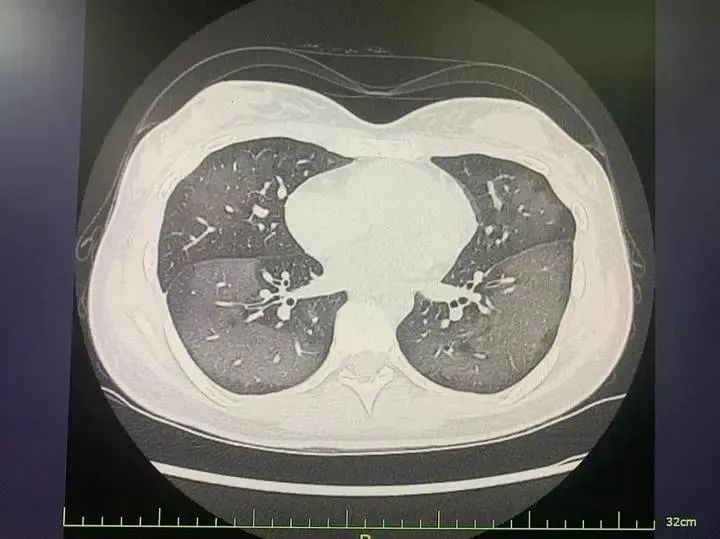

患者肺部CT

經CT檢查發現,麗麗的雙肺呈現大范圍白色樣病變,報告提示“白肺”,麗麗被診斷為“急性過敏性肺炎”。

陸遠強主任介紹,“白肺”是指在胸部X片或肺部CT等影像學檢查中,看到患者肺部呈現大范圍的白色陰影。急診科接診的“白肺”患者,多見于年齡較大、免疫力低下、有慢性病史或多種疾病共存的人群,年輕人因吸入防曬噴霧變“白肺”的病例并不多見。